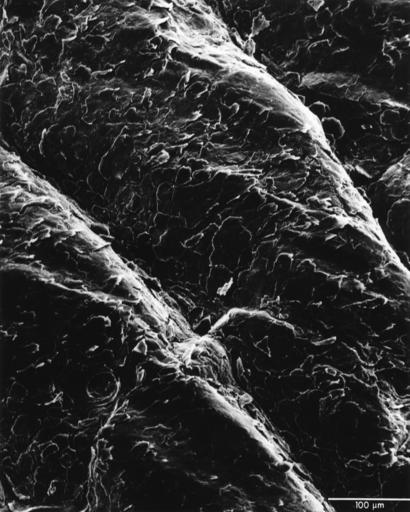

| Keywords: Skin surface (human).jpg A scanning electron micrograph of the surface of human skin Topics/Categories Anatomy -- Skin Cells or Tissue -- Abnormal Cells or Tissue Type B W Photo Source National Cancer Institute Dr Bruce Wetzel Photographer 1830 date Reuse Restrictions None - This image is in the public domain and can be freely reused Please credit the source and/or author listed above Dr Bruce Wetzel Photographer PD-USGov-HHS-NIH Media from National Cancer Institute Visuals Online Images uploaded by Fæ Human anatomy | ||||